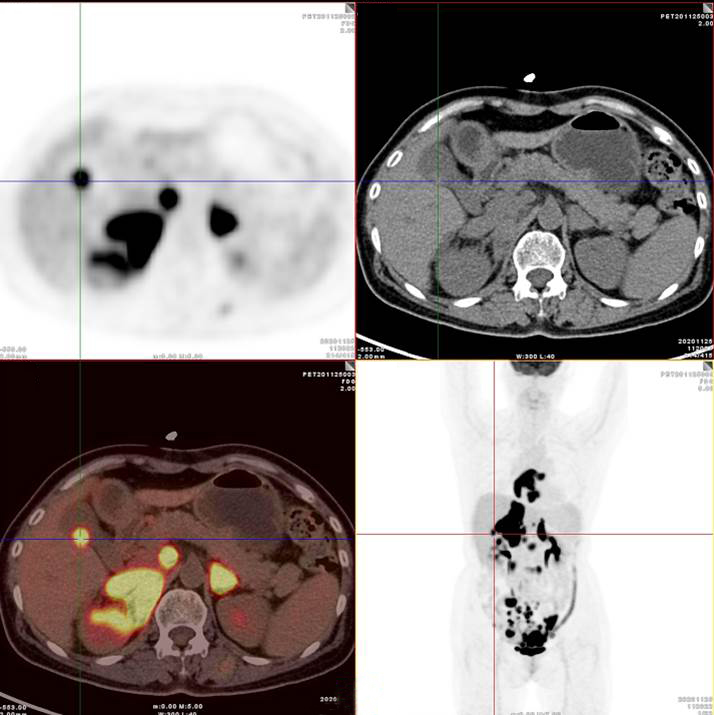

PET/CT影像圖

雙側(cè)腎上腺病灶、腹膜后淋巴結(jié)放射性攝取明顯增高

膽囊及雙腎上腺病灶、腹膜后淋巴結(jié)放射性攝取明顯增高

胃、雙腎上腺病灶、腹膜后淋巴結(jié)放射性攝取明顯增高